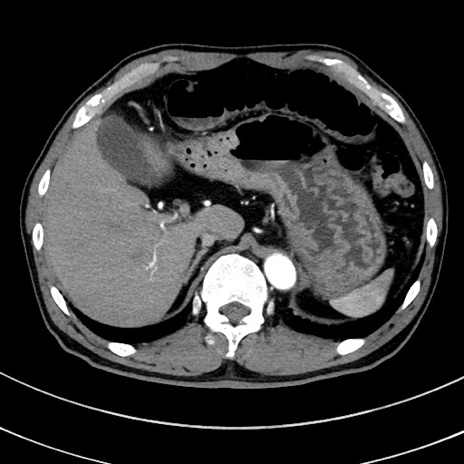

冠状断像